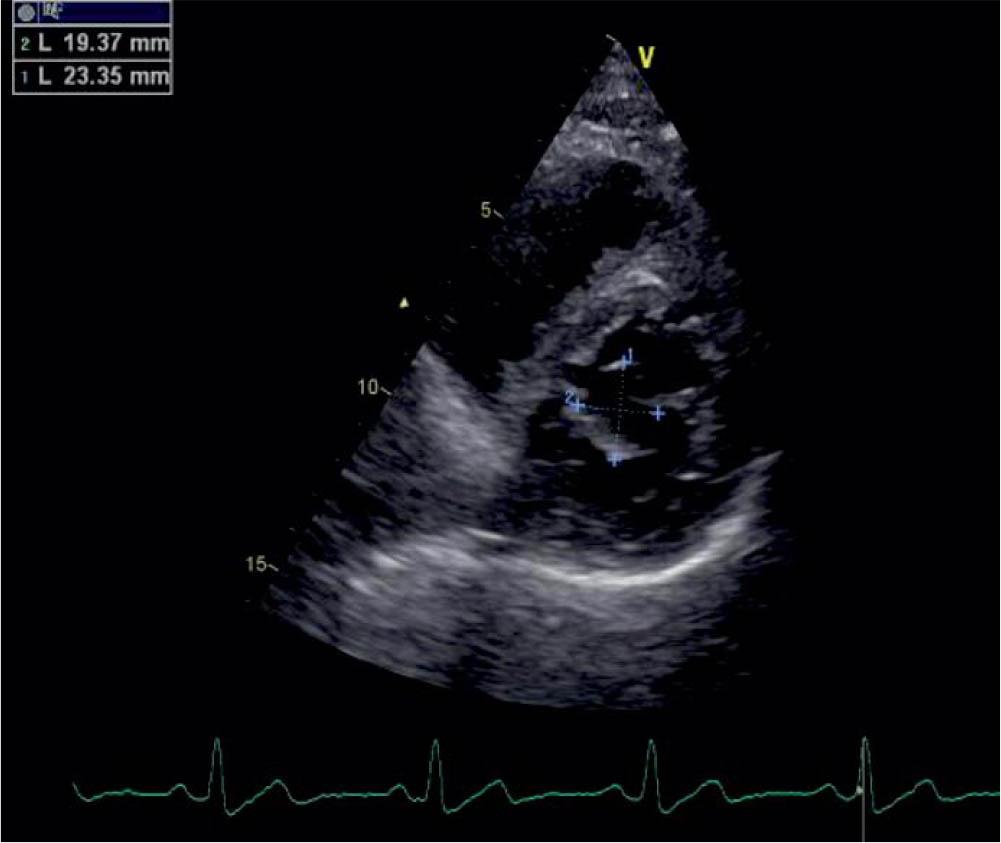

Figure 2